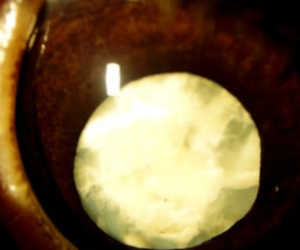

過熟白内障

混濁が強まり、水晶体が溶けてしまう時期です。水晶体核・皮質の萎縮・硬化、水晶体縮小、皮質の液化現象、モルガニー白内障などの状態になります。